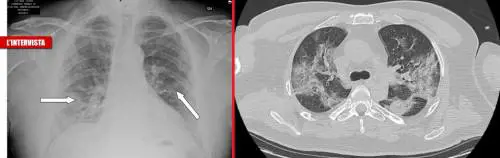

Abbiamo intervistato il dott. Franco Carnesalli, pneumologo all'Istituto Auxologico di Milano, che ci ha rivelato come il virus attacchi i polmoni, a volte in forma leggera, molte altre con broncopolmoniti. Spesso si scopre soltanto con una radiografia o Tac. E c'è un farmaco che potrebbe prevenirlo...

La forza "feroce" del Covid: "Rompe i muri dei polmoni"